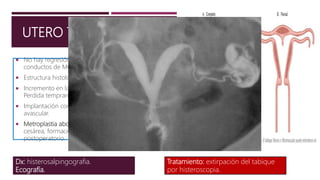

UTERO TABICADO

 No hay regresión de segmentos mediales de los

conductos de Muller fusionados.

 Estructura histológica fibrosa o fibromuscular.

 Incremento en las cifras de aborto espontaneo (42%).

Perdida temprana.

 Implantación completa o parcial en un tabique

avascular.

 Metroplastia abdominal: necesidad de practicar

cesárea, formación de adherencias pélvicas en el

postoperatorio.

Dx: histerosalpingografia.

Ecografía.

Tratamiento: extirpación del tabique

por histeroscopia.